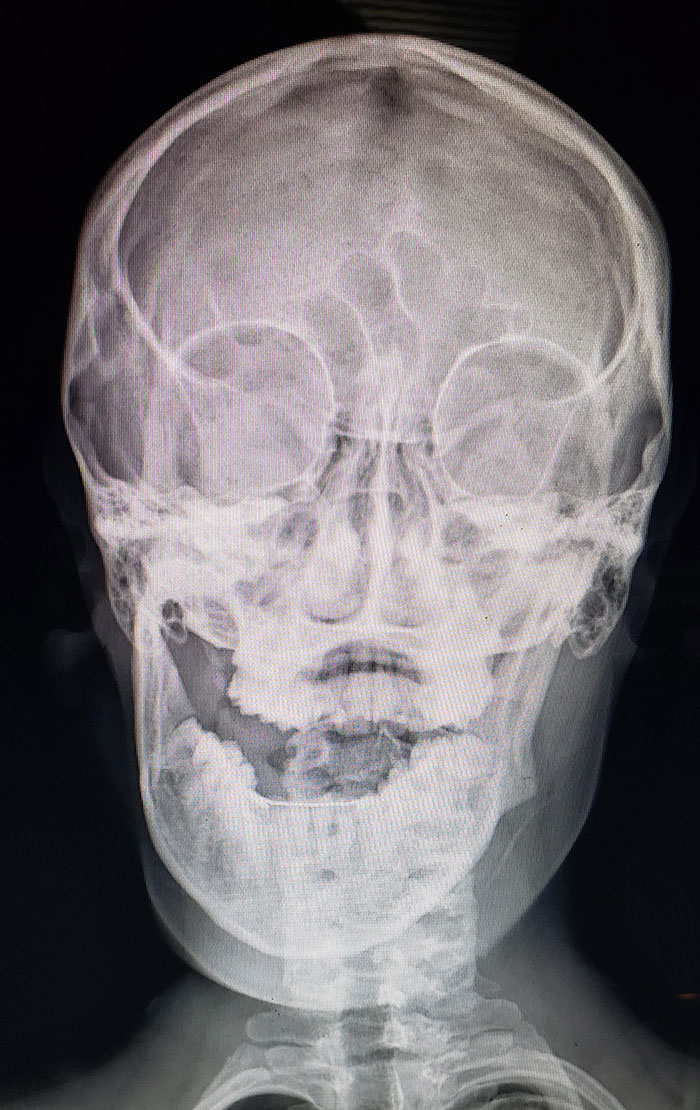

I Dislocated My Jaw... While Eating Cereal